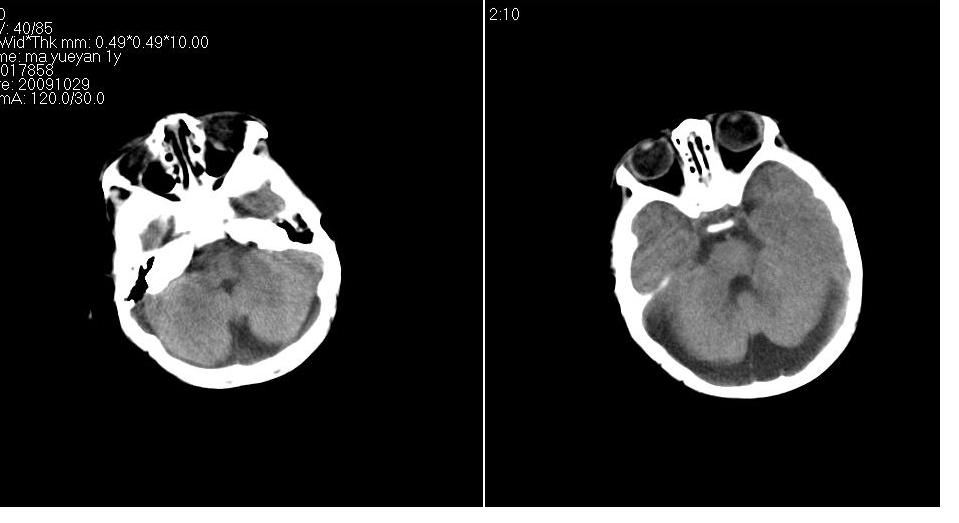

男 1岁,外伤就诊。智力正常,骨窗正常。

正常变异,大枕大池。鉴别:蛛网膜囊肿、双侧小脑发育不良。

蛛网膜囊肿一般是封闭的空间,张力较大,临近颅骨一般受压变薄。本例支持大枕大池

大枕大池与蛛网膜囊肿的主要区别就是看颅骨有没有压迹,如果有的话一般考虑蛛网膜囊肿。